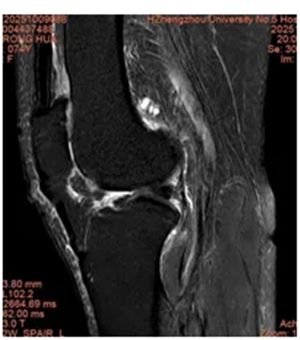

今年70多岁的刘阿姨,近些年膝关节疼痛的问题一直困扰着她的生活,遇天冷、运动稍多膝关节就疼痛难忍。前几天膝关节疼痛又加重了,刘阿姨多方打听后来到郑州大学第五附属医院骨科一病区找到徐明杰主任。刘阿姨一来就表达想尽快治疗的想法,又表示不愿做手术。徐明杰主任对刘阿姨进行了细致的检查、评估,制定了膝关节神经射频治疗方案。

借助C臂透视设备,精准地将射频针定位到膝关节射频治疗部位,操作无需切口,仅需一枚细针,不对周围组织造成损伤,整个操作无痛苦,患者几乎无不适或疼痛感觉。

操作过程中,徐明杰主任和郝壮宇医师在局麻下行穿刺后,将射频电极导入。予以脉冲射频治疗,整个过程仅需要几分钟。操作后患者即刻感觉疼痛明显缓解。术后第二天患者下床活动自如,疼痛感消失,上下楼梯、蹲起等动作都能更轻松完成,生活质量大幅提升。